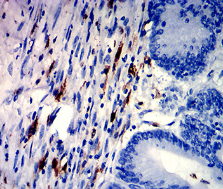

IHC    1/200 - 1/1000